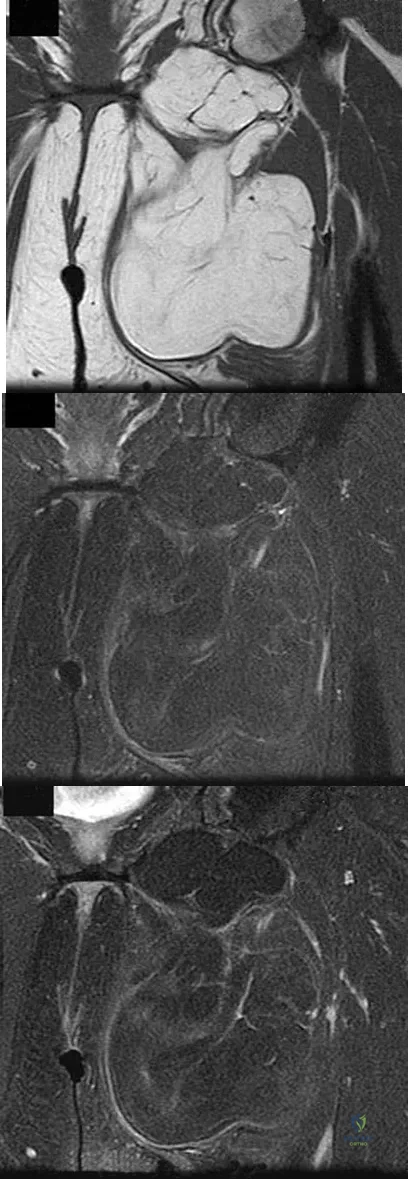

Figures 24a through 24c show the coronal T1-weighted, T2-weighted fat-saturated, and T1-weighted fat-saturated gadolinium MRI scans of the proximal thigh of a 52-year-old woman who reports a mass in the medial thigh and groin area. She notes that the fullness has grown in size over the course of many months. Based on these findings, what is the most likely diagnosis?

Explanation